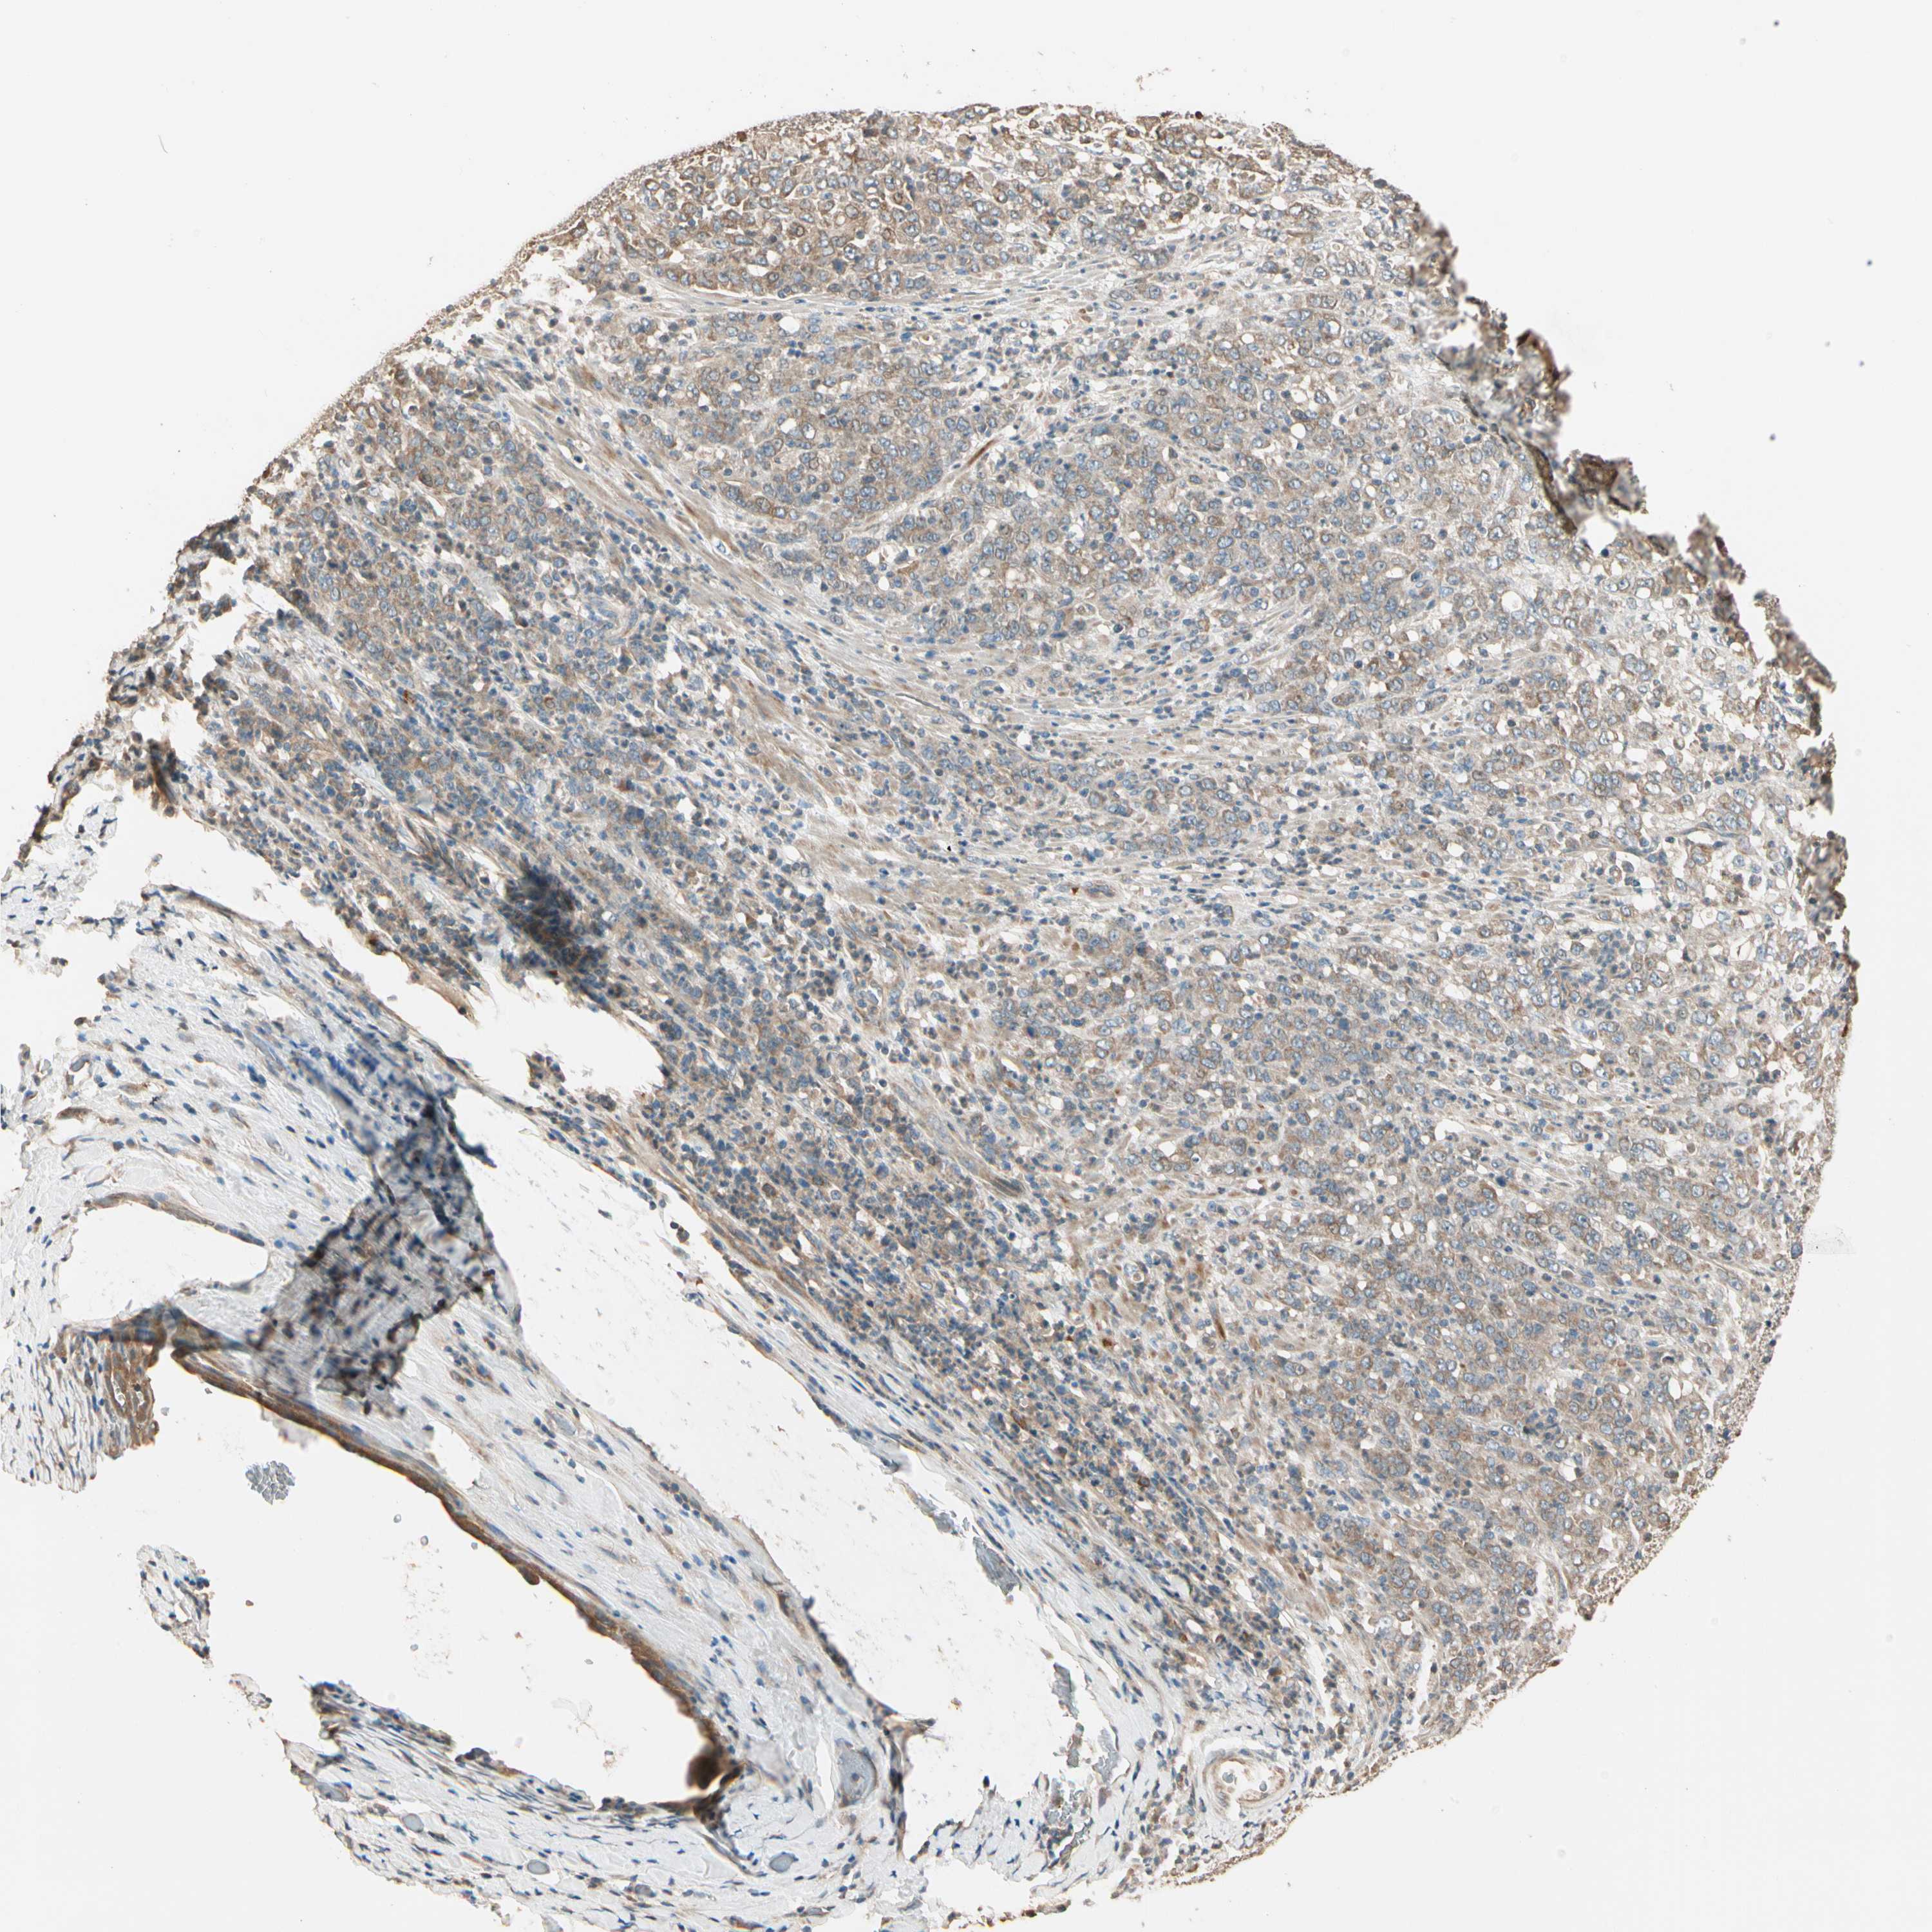

STOMACH CANCER - Protein expressioni

A mouse-over function shows sample information and annotation data. Click on an image to view it in a full screen mode. Samples can be filtered based on level of antibody staining by selecting one or several of the following categories: high, medium, low and not detected. The assay and annotation is described here.

Antibody stainingi

Antibody staining in the annotated cell types in the current human tissue is reported as not detected, low, medium, or high, based on conventional immunohistochemistry profiling in selected tissues. This score is based on the combination of the staining intensity and fraction of stained cells.

Each image is clickable and will lead to virtual microscopy that enables deeper exploration of all samples and also displays staining intensity scores, fraction scores and subcellular localization as well as patient and tissue information for each sample.

Antibody HPA006746

Antibody CAB009805

Staining

High

Medium

Low

Not detected

Intensity

Strong

Moderate

Weak

Negative

Quantity

>75%

75%-25%

<25%

None

Location

Nuclear

Cytoplasmic/membranous

Cytoplasmic/membranous,nuclear

Adenocarcinoma, NOS

Adenocarcinoma, High grade